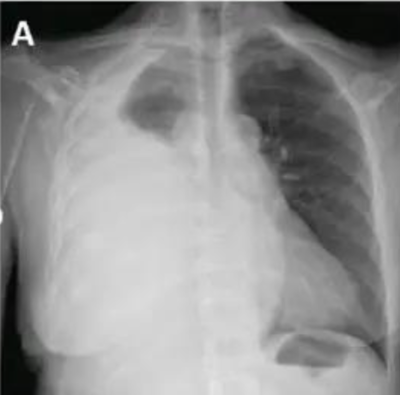

2) La 1ère image tirée du prof est un pneumothorax

GAUCHE, tu as bien raison et je ne dis pas dans la fiche que c'est un pneumothorax droit, on pourrait le penser car les 2 images du cours sont côte à côte et le scanner est un pneumothorax droit mais ce n'est pas le cas. Tu vois bien une hypodensité à gauche alors qu'à droite tu vois des petits points blancs correspondant aux alvéoles pulmonaires.

La masse blanche de cette 1ère image me laisse penser qu'il y a aussi un épanchement pleural liquidien sur cette radio avec une hyperdensité en base droite avec un comblement du cul-de-sac pleural.